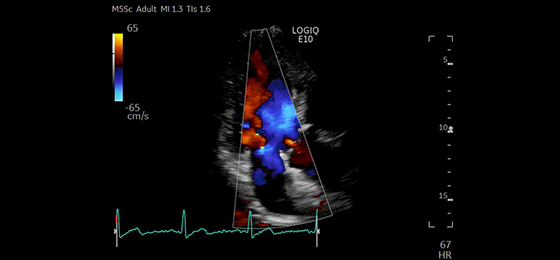

Dual Color Flow Jets, M5Sc-D

Apical 4CH CF Tricuspid Valve, M5Sc-D